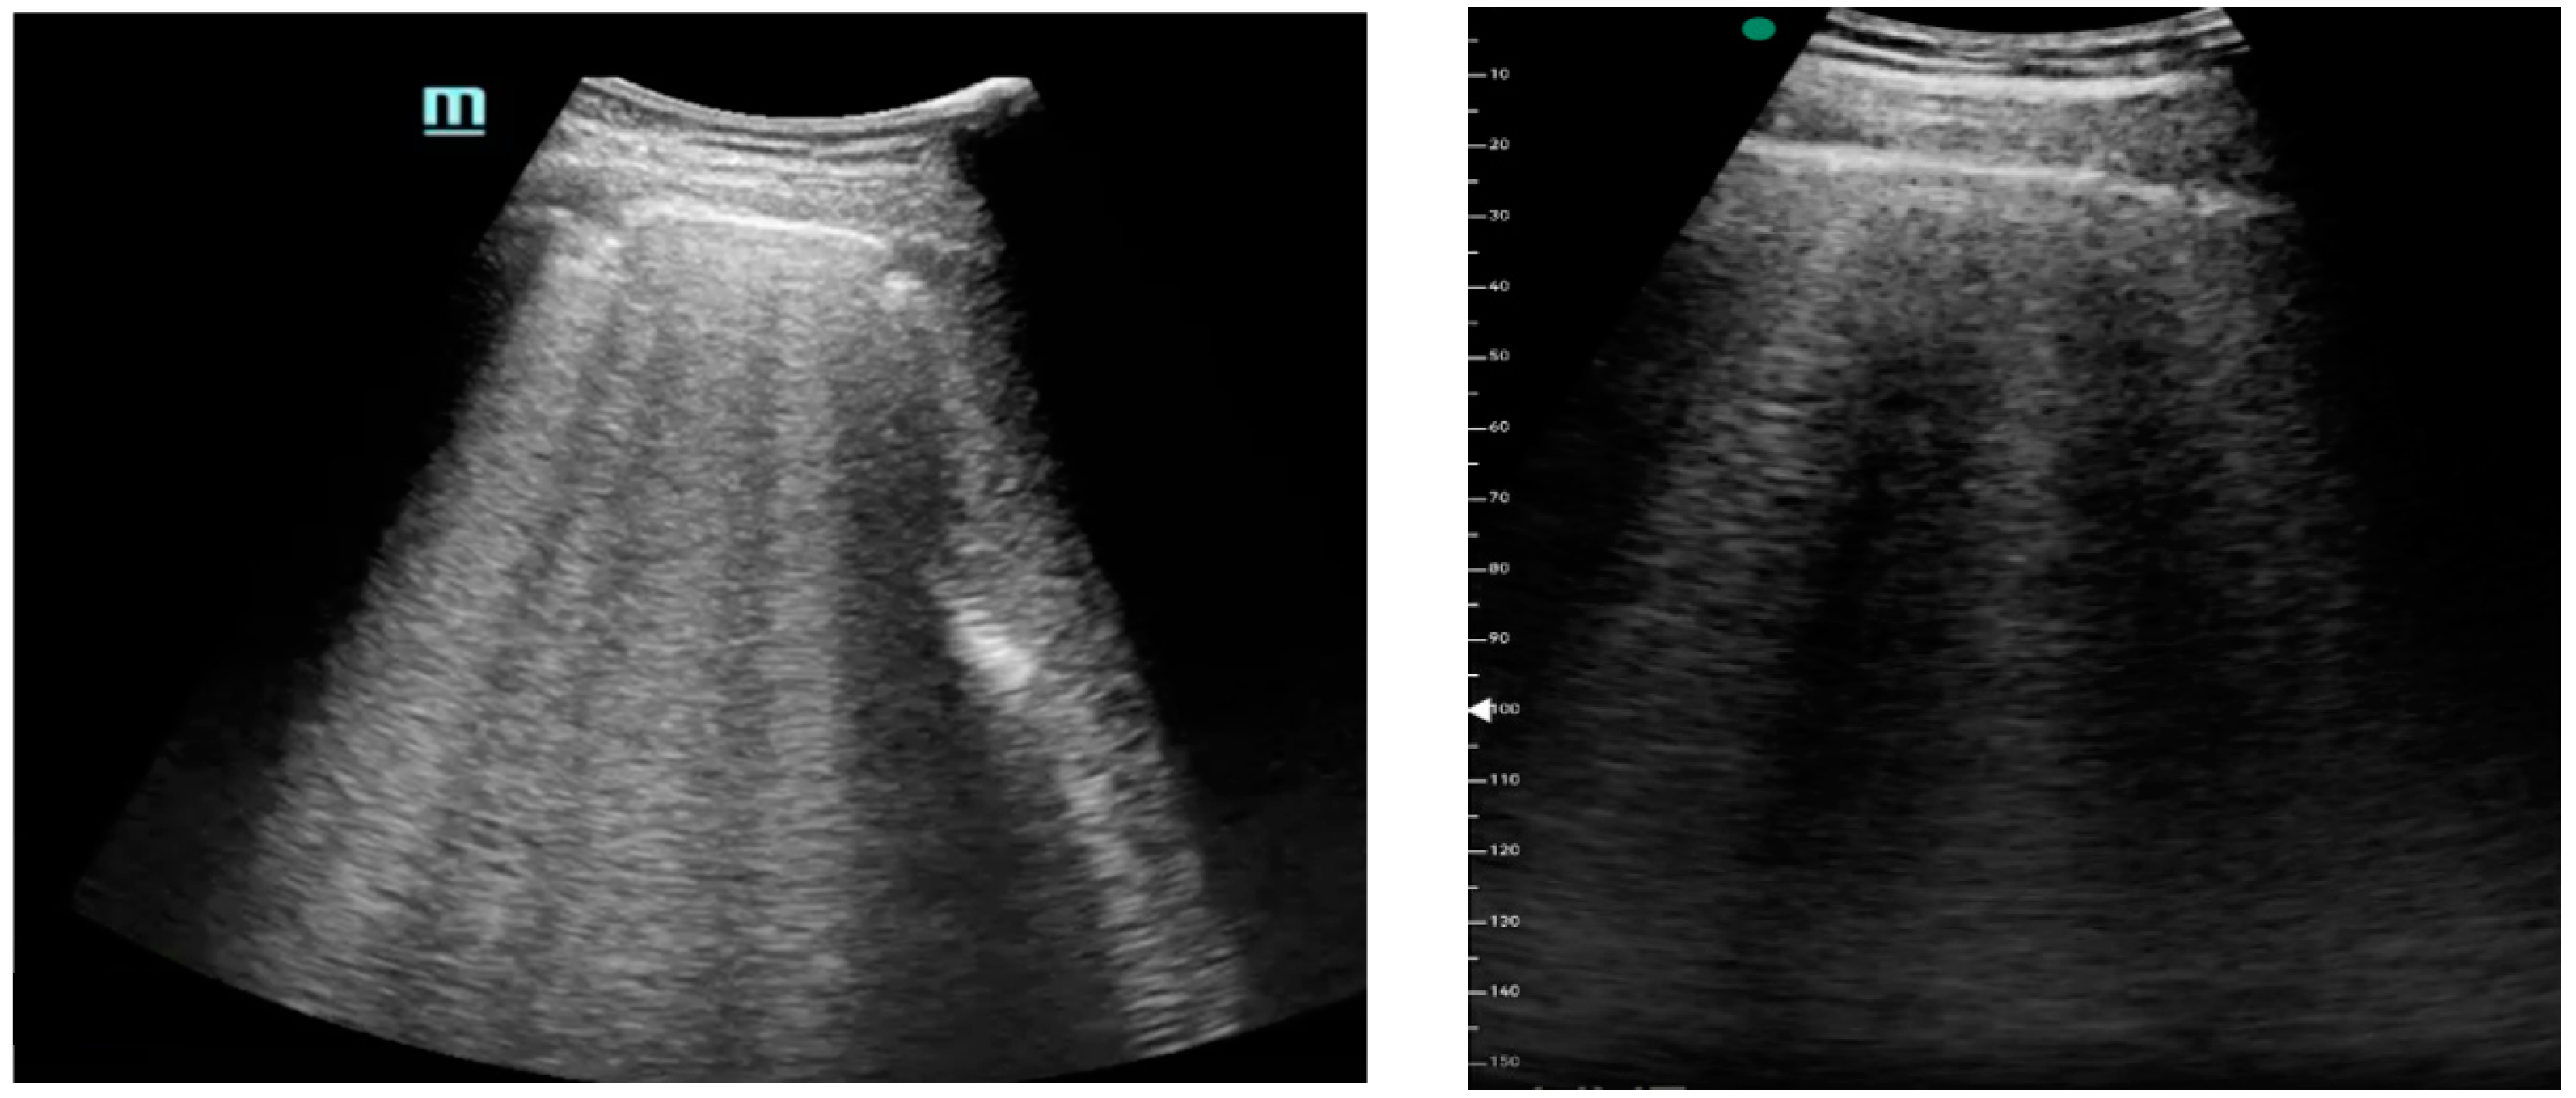

Figure 1, Figure 2 and Figure 3 exhibit characteristic examples of ultrasound still images from the videos captured via a standard ultrasound (left side) and portable handheld device (right side). Quality may slightly differ from that of the videos as these are still images.

Figure 1.

B-lines.